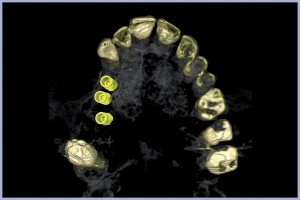

Al 5° giorno di terapia antibiotica, si esegue l’estrazione dell’elemento dentale con rimozione del granuloma apicale con toiletta chirurgica ed emostasi con spugnette di fibrina e sutura in seta con punti staccati; il paziente viene congedato con protesi parziale immediata per, poi, eseguire impianti post-estrattivi differiti. Il paziente per motivi familiari si ripresenta dopo circa un anno. Dopo una Tomografia Computerizzata Cone-Beam in studio, si valuta la quantità e la qualità dell’osso nella zona interessata all’implantologia e si pianifica una chirurgia implantare mini invasiva software assistita pianificata con software 3Diagnosys® (3DIEMME® Srl, Cantù (Co)). Si opta per il sistema implantare Exacone® Leone poiché, data la sua affidabilità e semplicità di esecuzione chirurgica, ben si presta a essere utilizzato in chirurgia guidata. Si prendono le impronte per la realizzazione dei modelli per la Dima Radiologica e si riesegue Tac Cone Beam. I file dicom risultati dell’esame radiologico vengono importati nel software 3Diagnosys® e si esegue il progetto implantare in posizione 14; 15; 16 con impianti Exacone® di dimensioni rispettivamente di: 4,1×12 mm; 4,1×12 mm; 4,1×10 mm.

- Fig. 39 – Immagine 3D post-intervento, vista inferiore

- Fig. 40 – Pianificazione 3D, vista inferiore

- Fig. 43 – Immagine 3D post-intervento, vista superiore

- Fig. 44 – Pianificazione 3D, vista superiore